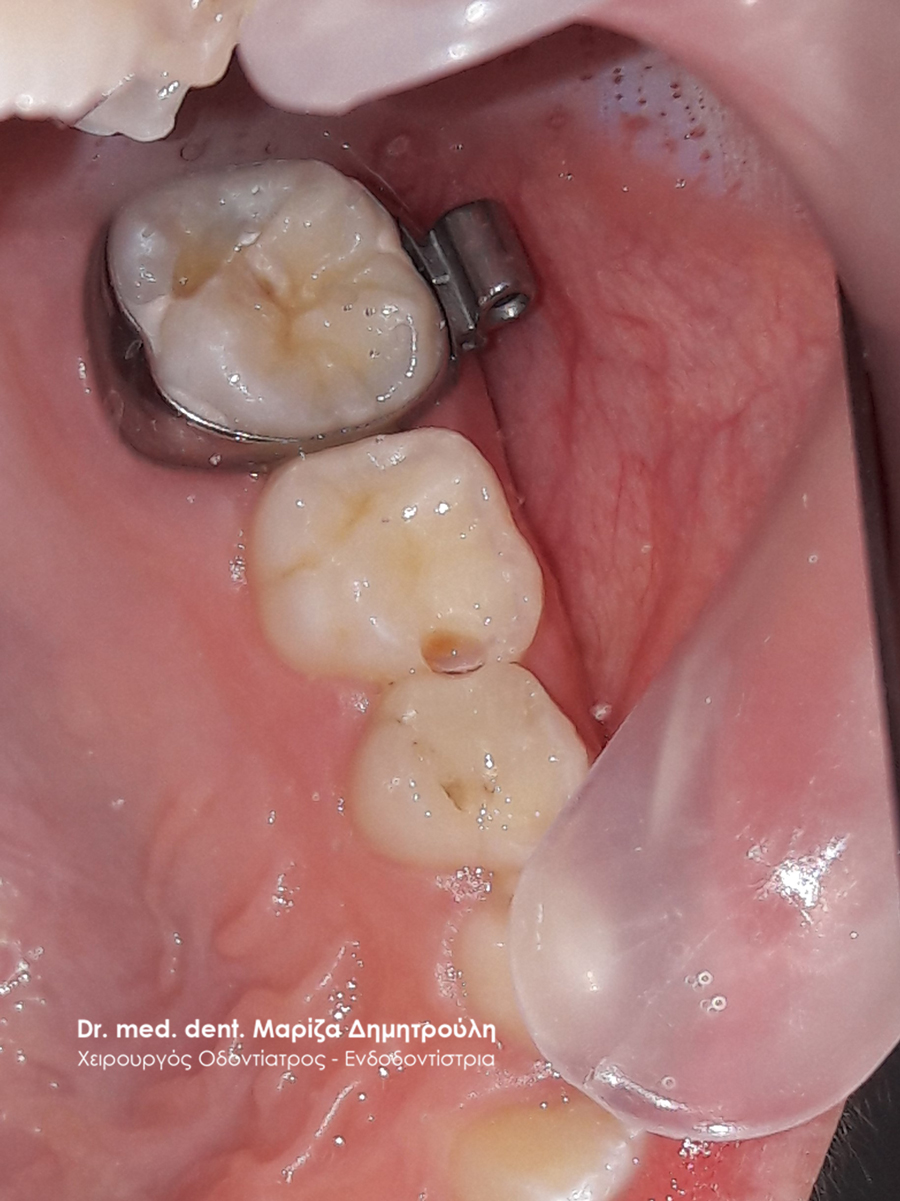

Κορίτσι ηλικίας 9 ετών αναφέρει οτι πονάει στην πάνω αριστερή πλευρά του στόματος της όταν μασάει. Μετά την κλινική εξέταση διαπιστώθηκε η ύπαρξη 2 τερηδονισμένων δοντιών. Στον πρώτο μόνιμο αριστερό γομφίο είναι εμφανής η ύπαρξη τερηδόνας, της οποίας η έκταση αποδείχτηκε αρκετά βαθιά κατά τη διάνοιξη του δοντιού. Στο δεύτερο νεογιλό (παιδικό) γομφίο παρατηρήθηκε η ύπαρξη τερηδονικής κοιλότητας μεσαίου βάθους.

Μετά την απομάκρυνση της τερηδόνας από τα δύο δοντάκια πραγματοποιήθηκαν λευκά σφραγίσματα σύνθετης ρητίνης.

ΠΡΙΝ

ΜΕΤΑ